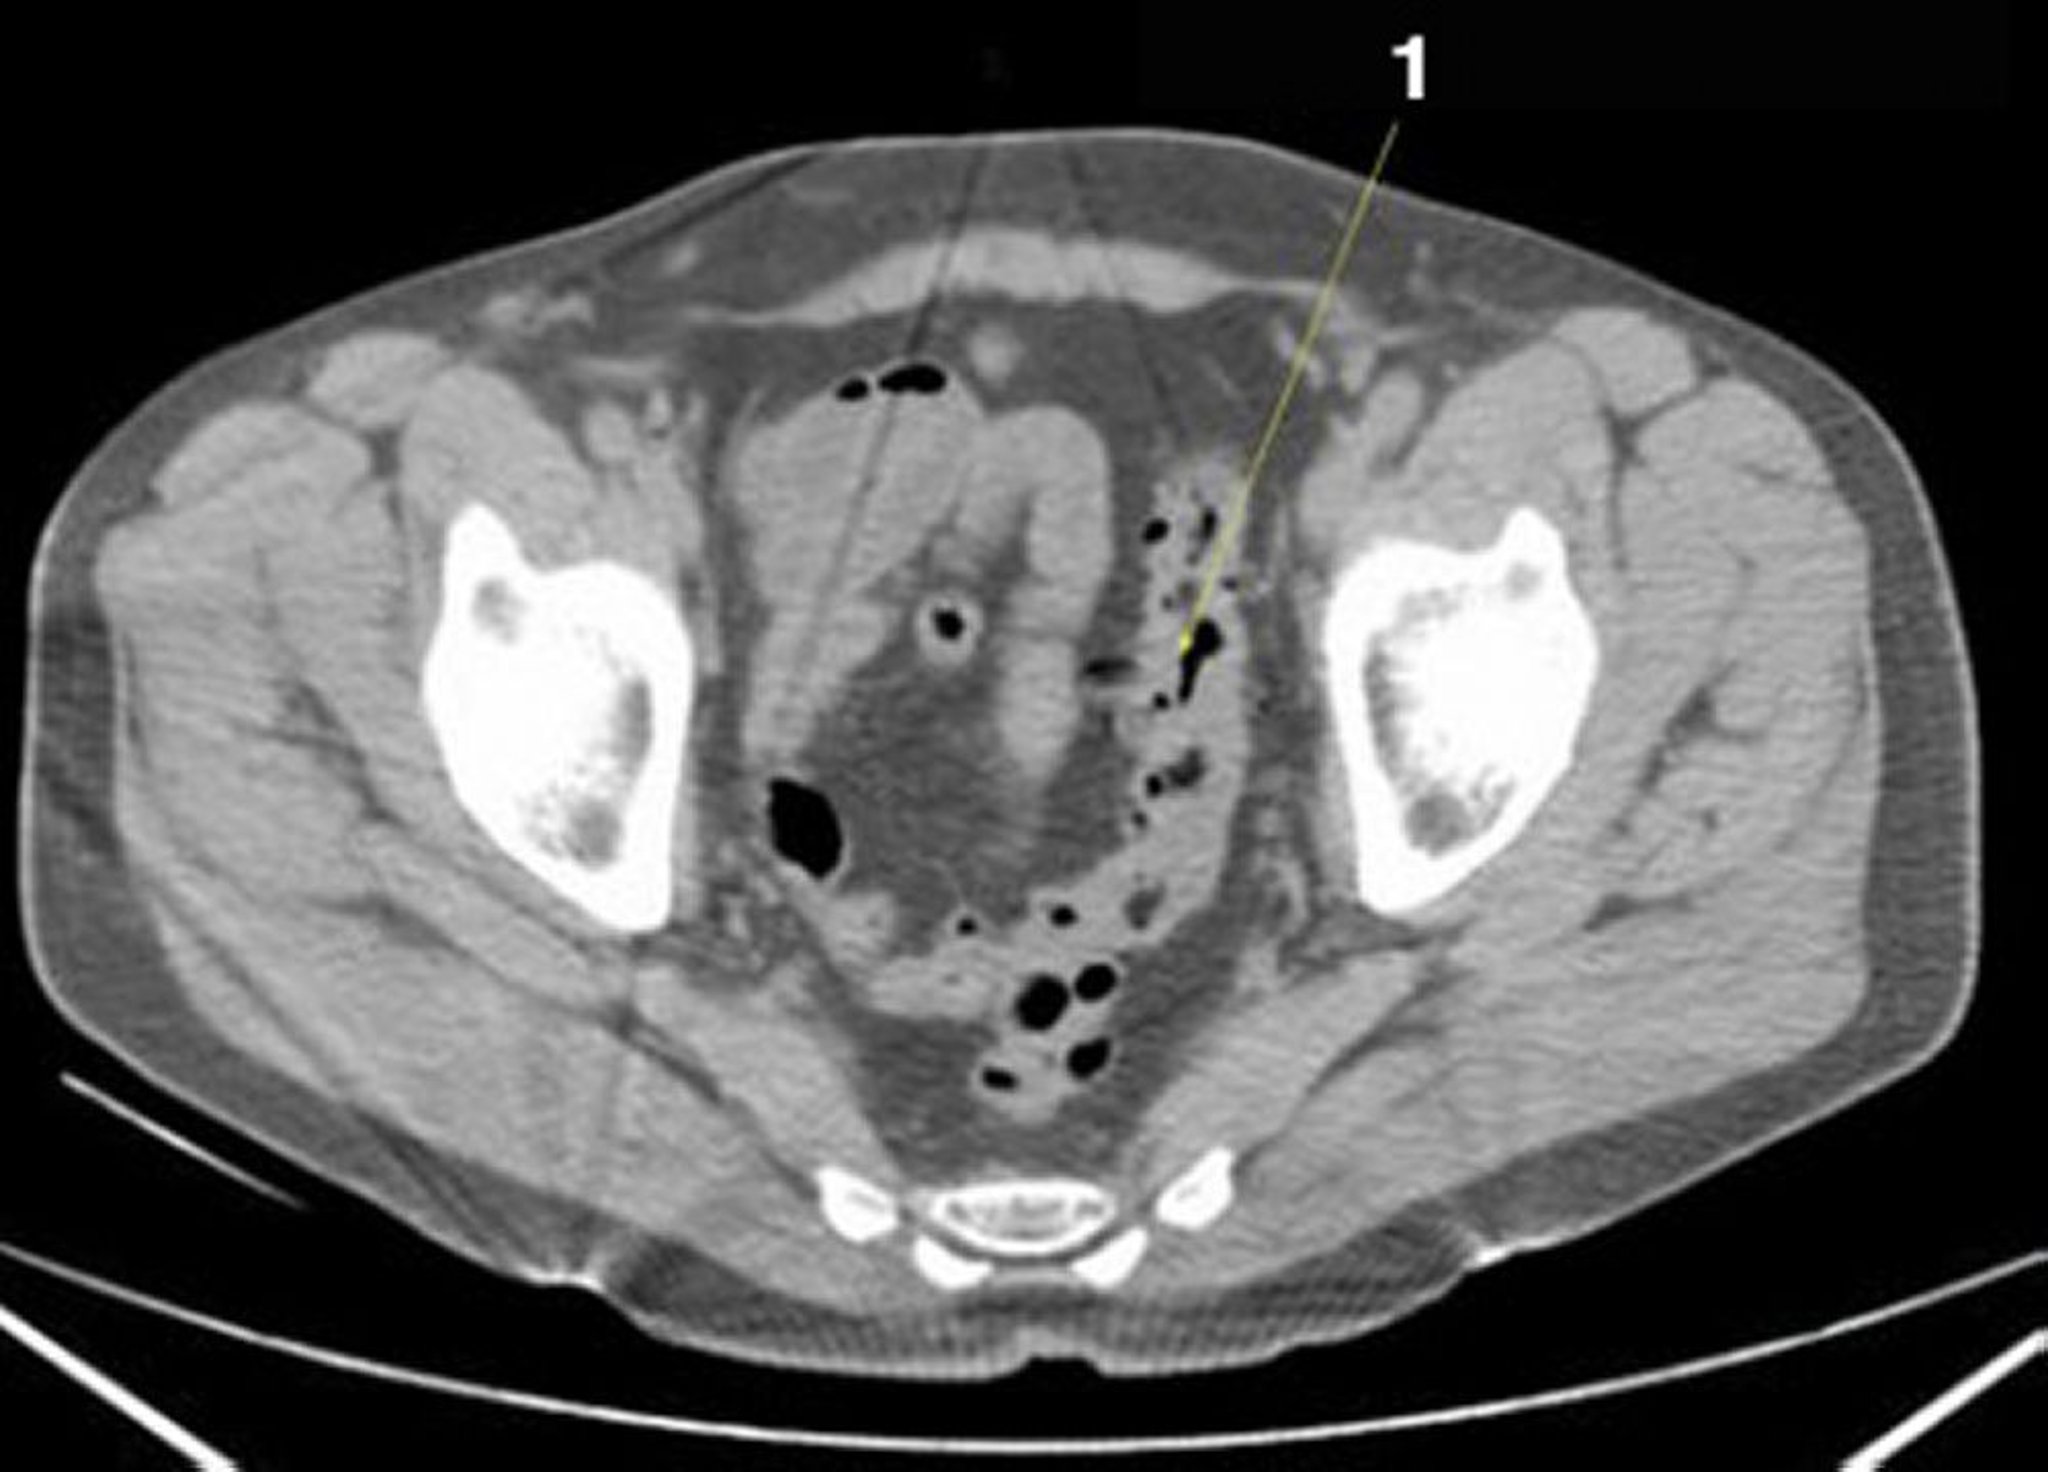

正常解剖を示した腹部および骨盤の単純CT画像(スライド25)

1 = S状結腸。